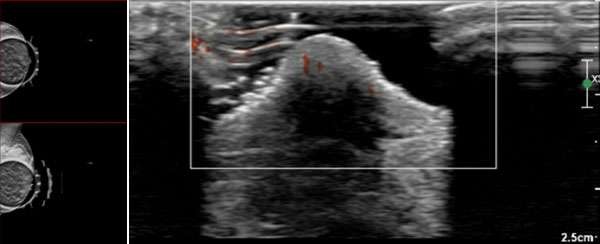

The mammographic findings of Paget’s disease include skin thickening in the nipple areolar complex region, nipple retraction, underlying suspicious calcifications, or a discrete mass. The ultrasound findings include nonspecific heterogeneity of the breast parenchyma, a mass, dilated ducts, and skin thickening or hypervascularity in the nipple areolar complex (Figure 3). Breast MRI may assist in further evaluation in the setting of negative mammogram and ultrasound findings (Figure 4).

WU: Skin Change Figure 3

Figure 3. Left image demonstrates spot CC and MLO mammogram views, with corresponding ultrasound on the right image, of the left breast in a 67-years-old female who was seen for diagnostic evaluation of new left nipple changes of redness, swelling, but no pain on exam. Approximately 3 weeks of topical steroid treatment did not improve the skin changes. There are no significant findings on diagnostic mammogram spot images of the nipple-areolar complex. On ultrasound there is notable hypervascularity. A punch biopsy of the nipple was performed a week later, confirming the diagnosis of Paget’s disease of the breast.